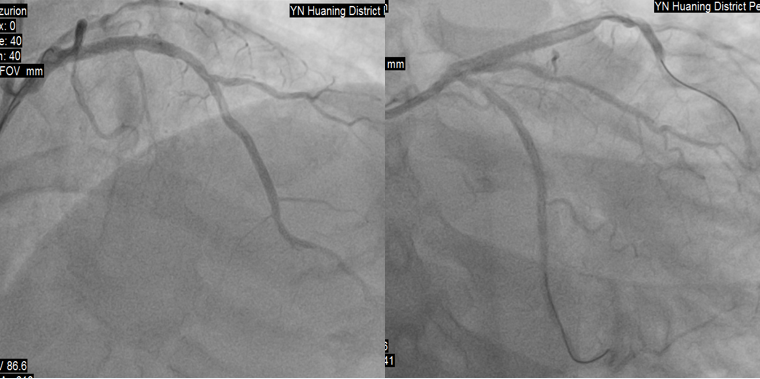

虽然患者胸痛明显缓解,考虑到梗死面积大,于11:20送达导管室,冠脉造影示:均势型,右冠全程弥漫性病变,最狭窄处50%,中段囊性扩张,血流3级;左主干未见明显异常;前降支近段次全闭塞,血流3级;回旋支中段次全闭塞,血流3级。

造影显示溶栓再通,12:20完成前降支、回旋支PCI手术。